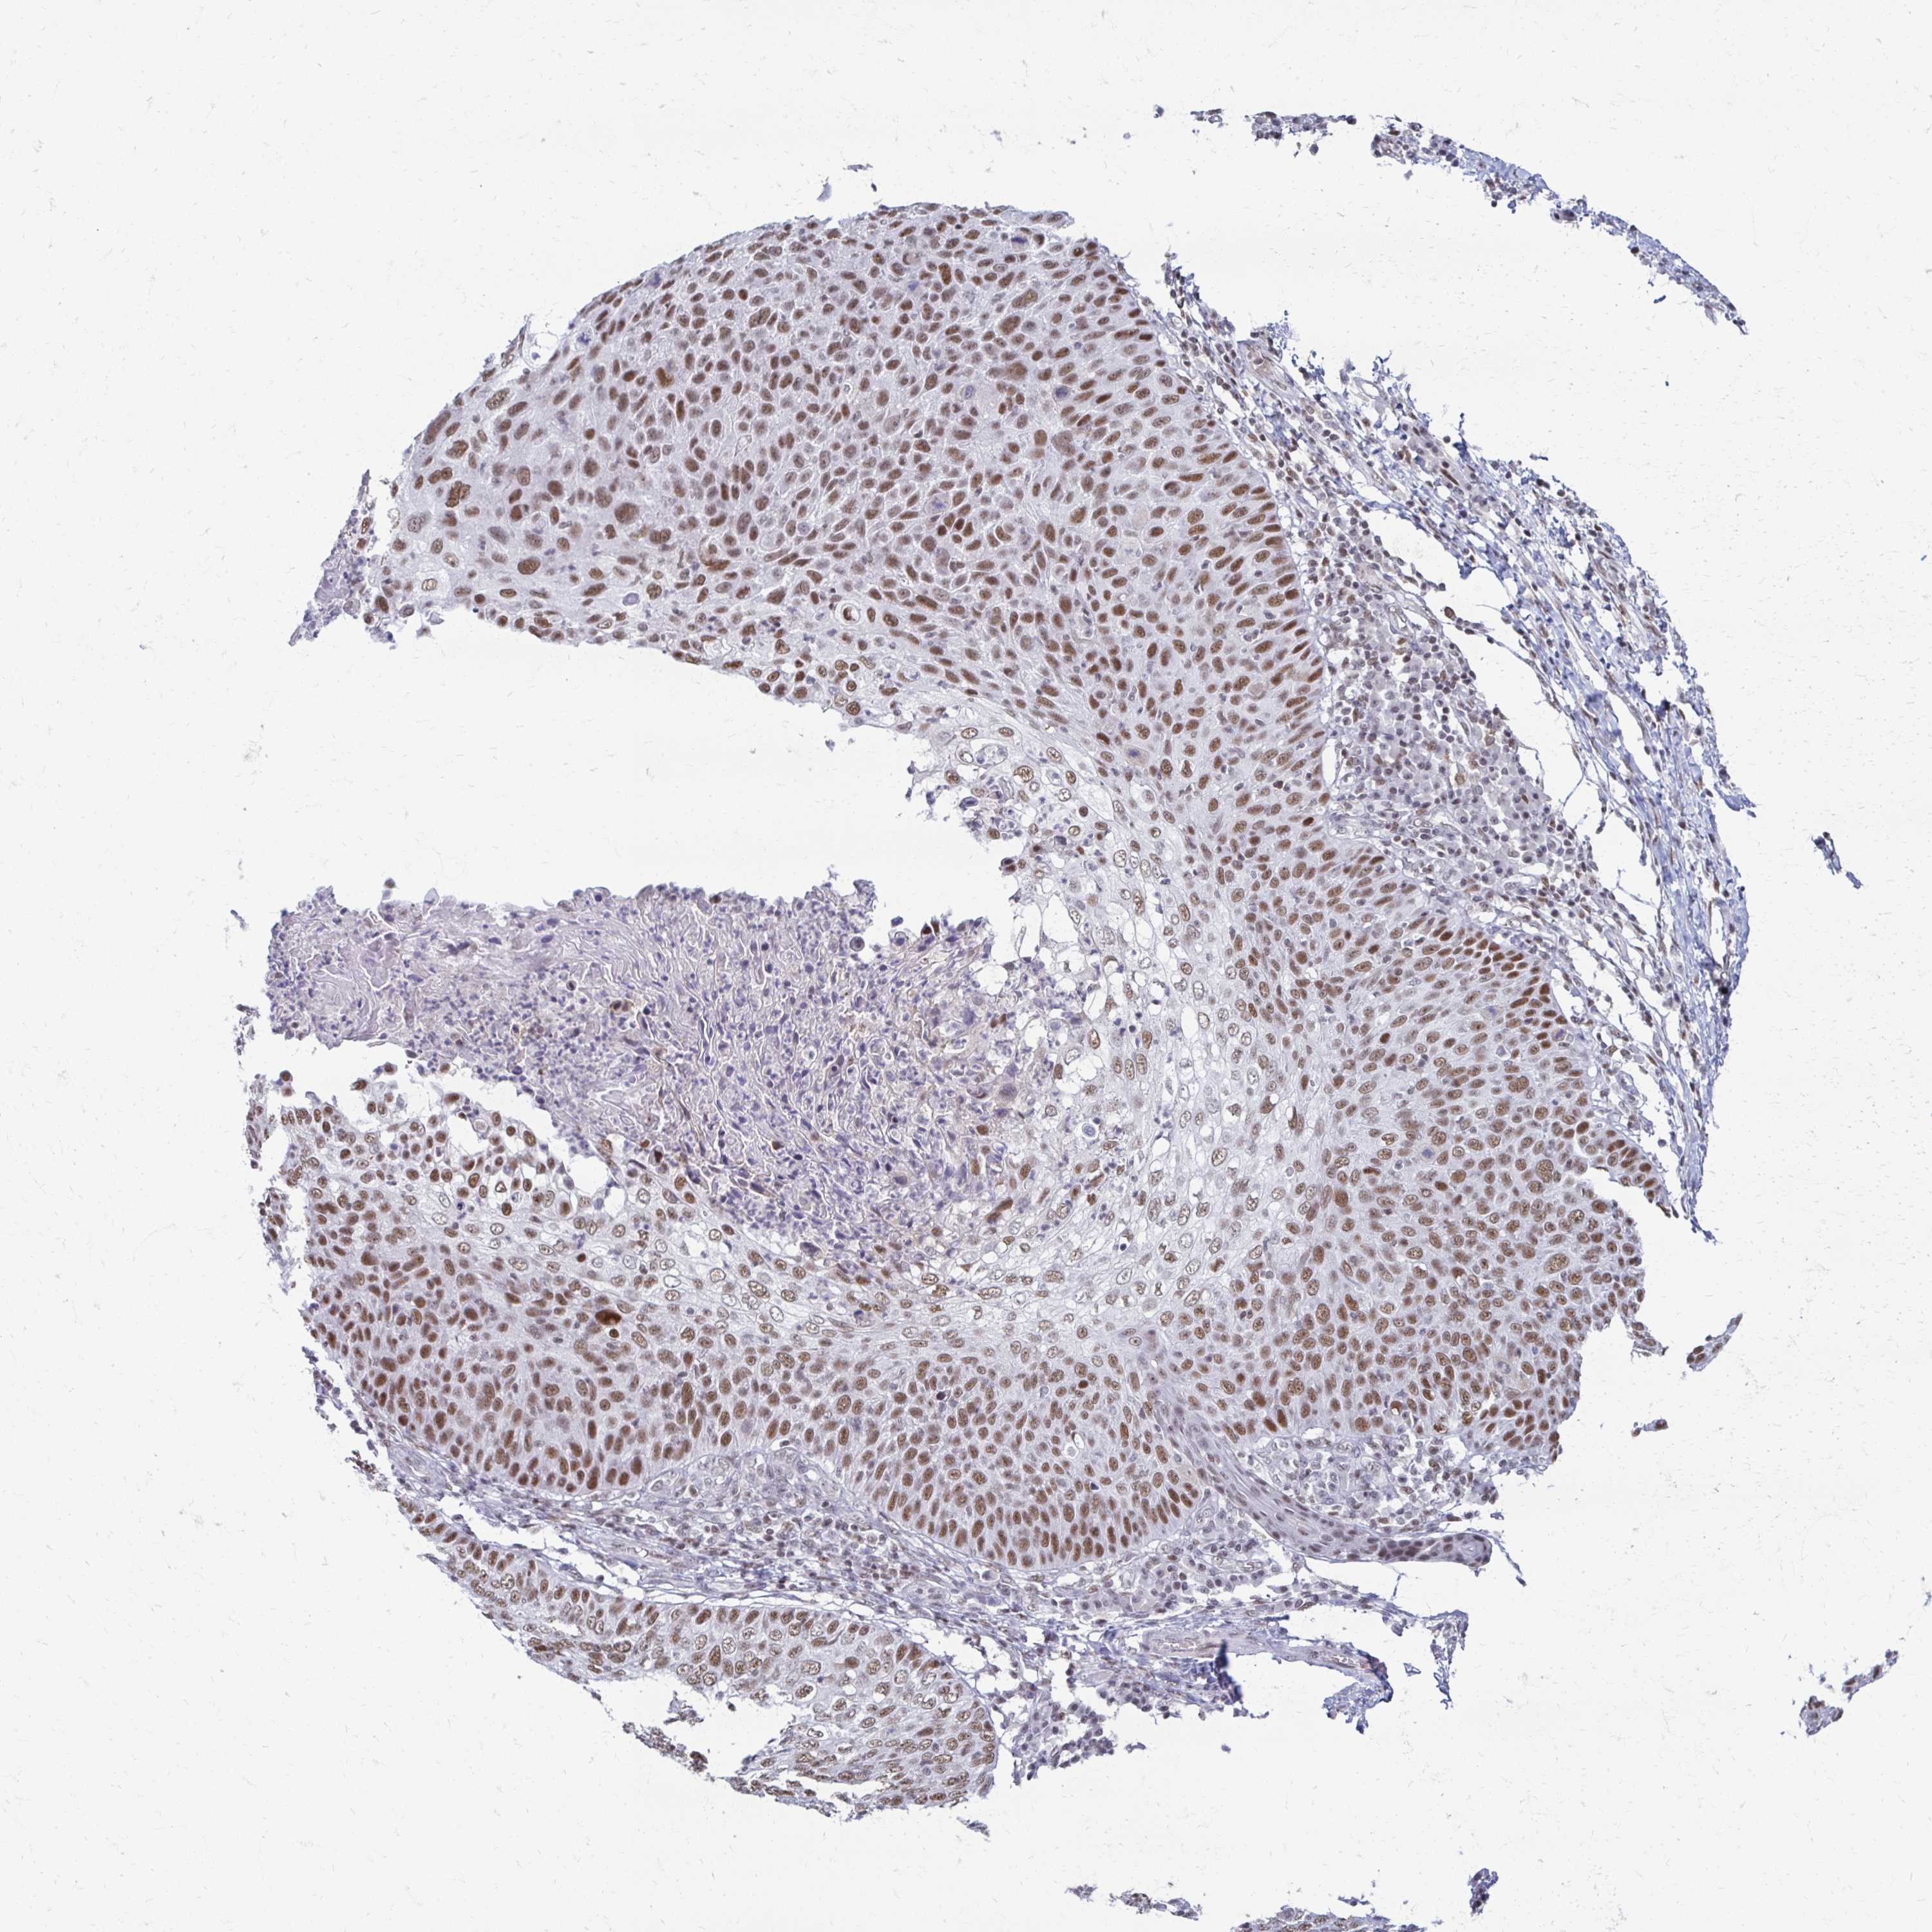

SKIN CANCER - Protein expressioni

A mouse-over function shows sample information and annotation data. Click on an image to view it in a full screen mode. Samples can be filtered based on level of antibody staining by selecting one or several of the following categories: high, medium, low and not detected. The assay and annotation is described here.

Antibody stainingi

Antibody staining in the annotated cell types in the current human tissue is reported as not detected, low, medium, or high, based on conventional immunohistochemistry profiling in selected tissues. This score is based on the combination of the staining intensity and fraction of stained cells.

Each image is clickable and will lead to virtual microscopy that enables deeper exploration of all samples and also displays staining intensity scores, fraction scores and subcellular localization as well as patient and tissue information for each sample.

Antibody HPA052757

Basal cell carcinoma